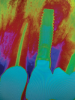

In this case, a dental implant that had been placed 10 years prior was functional, stable, and esthetically acceptable to the patient. However, a significant fistula was present on the facial-apical aspect of the ridge in the maxillary lateral incisor area. This area was painfully sensitive to touch and demonstrated purulence when squeezed. To evaluate the lesion, first, a conventional digital radiograph was acquired, which revealed an apical radiolucency at the apex of the implant (Figure 1). Further analysis using cone-beam computed tomography (CBCT) demonstrated a fistula from that site to the oral environment (Figure 2). Treatment options were discussed, including removal of the implant, followed by grafting, a healing period, and replacement of the implant and implant-retained crown. If this option was selected, a transitional appliance would need to be created. Another option was to attempt to salvage the implant and implant crown by treating the infection and grafting the site to create a new boney wall and eliminate the fistula. Ultimately, the patient accepted this option to attempt to salvage the fixture and crown.

Peri-implantitis was not the culprit behind the creation of this infected site; the lesion developed as a result of the position of the implant. Although the implant was initially stable upon placement, it was angled such that its apex had penetrated through the facial plate of bone. Without a sagittal CBCT analysis or a releasing flap performed to evaluate the initial placement, the surgeon could easily miss this. Regardless, the circumstances warranted evaluation of the apical aspect of the implant to attempt to salvage it.

(2.) Preoperative CBCT analysis demonstrating a fistula from the site of the radiolucency to the oral environment.

Figure 2